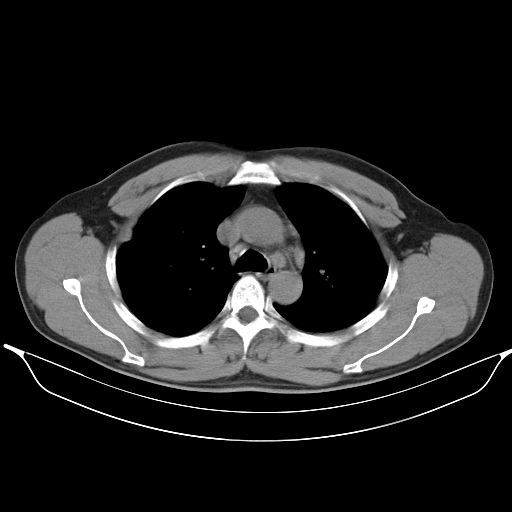

标题: CT25490:男,40岁,体检发现;无其它不适。 [打印本页]

标题: CT25490:男,40岁,体检发现;无其它不适。

考虑右下肺周围性肺癌并肺内多发转移,纵隔淋巴结转移!

支持 !考虑右下肺周围性肺癌并肺内多发转移,纵隔淋巴结转移,(气管前腔静脉后,隆突下,主动脉弓下都有了)